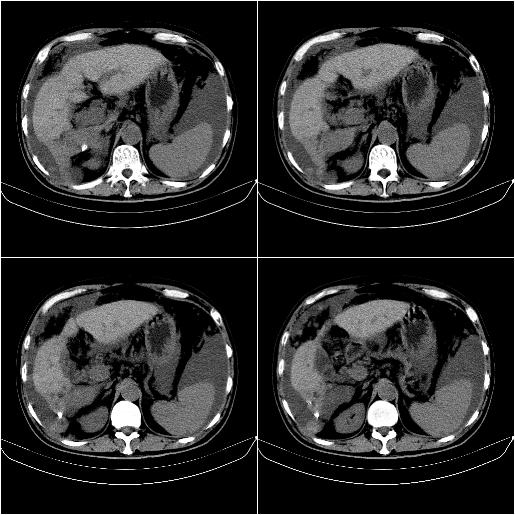

标题: CT21651:M,67Y,肝癌9月,介入术后3月。

m,67y,肝癌9月,介入术后3月。现腹胀、纳差、腹泻。

门静脉有很大的瘤栓,膈肌及膜膜有转移,不用再做了.

情况不好,门静脉癌栓、腹膜转移。

1)肝癌介入治疗术后碘油沉积不良。2)门静脉瘤栓形成,腹膜广泛性转移。3)肝硬化,脾大,腹水。4)慢性胆囊炎。